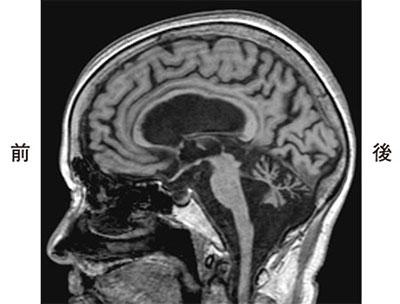

つまずきやすさを主訴に来院した70歳の患者の頭部MRIのT1強調矢状断像を示す。この患者で主訴に関連のある症状はどれか。

1

運動失調

2

感覚障害

3

視野障害

4

前庭障害

5

歩行失行